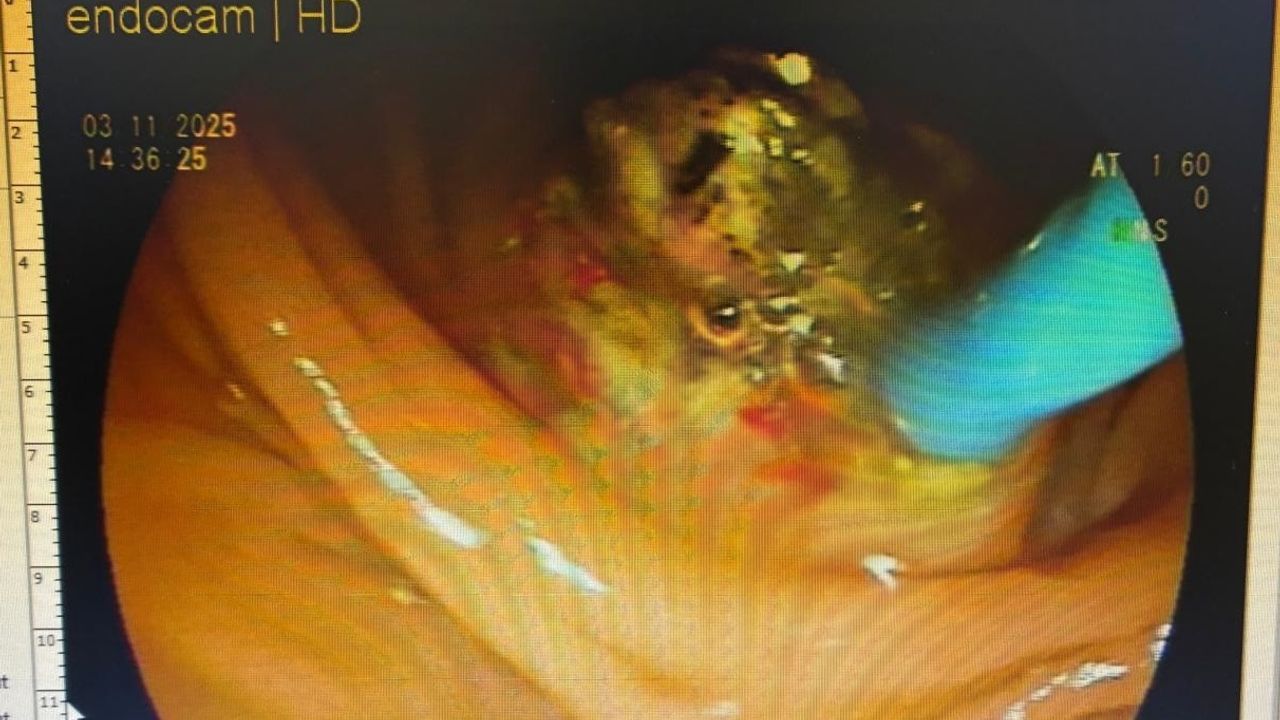

Vücudunda ters yönde bulunan safra kesesinden ameliyata alındığını söyleyen uzman doktor Akbay, “Hastamız karın ağrısı şikayetiyle hastanemize başvurdu. Çekmiş olduğumuz MR'da karın iç organlarının tam tersi yerleşmiş olduğunu gördük. ‘Situs inversus totalis’ denilmektedir buna. Sağda olması gereken karaciğer ve safra kesesi sol tarafta, solda olması gereken kalp ise sağ tarafta yerleşmişti. Bu hastamızın safra kanalında taşı olup, akut pankreatit atağı geçirmekteydi. Safra kanalındaki taşlarını ileri endoskopik yöntem olan ERCP işlemiyle başarılı bir şekilde ameliyat ettik" ifadelerini kullandı.

Hastadaki durumunun dünyada ender görüldüğünü söyleyen doktor Akbay, "Hem organların ters tarafta olması, aynı zamanda safra kanalında taş ve pankreklatları geçirmesi çok nadir görülen bir durumdur. Dolayısıyla ileri endoskopik yöntem olan ERCP işlemi içinde hastanın tam ters pozisyonda, başarılı bir şekilde yatırdık. Odanın dizaynını ona göre ayarladık, işlem oldukça zor olmasına rağmen başarılı bir şekilde işlemimizi yaptık, hastamız sağlığına kavuştu" diye konuştu.